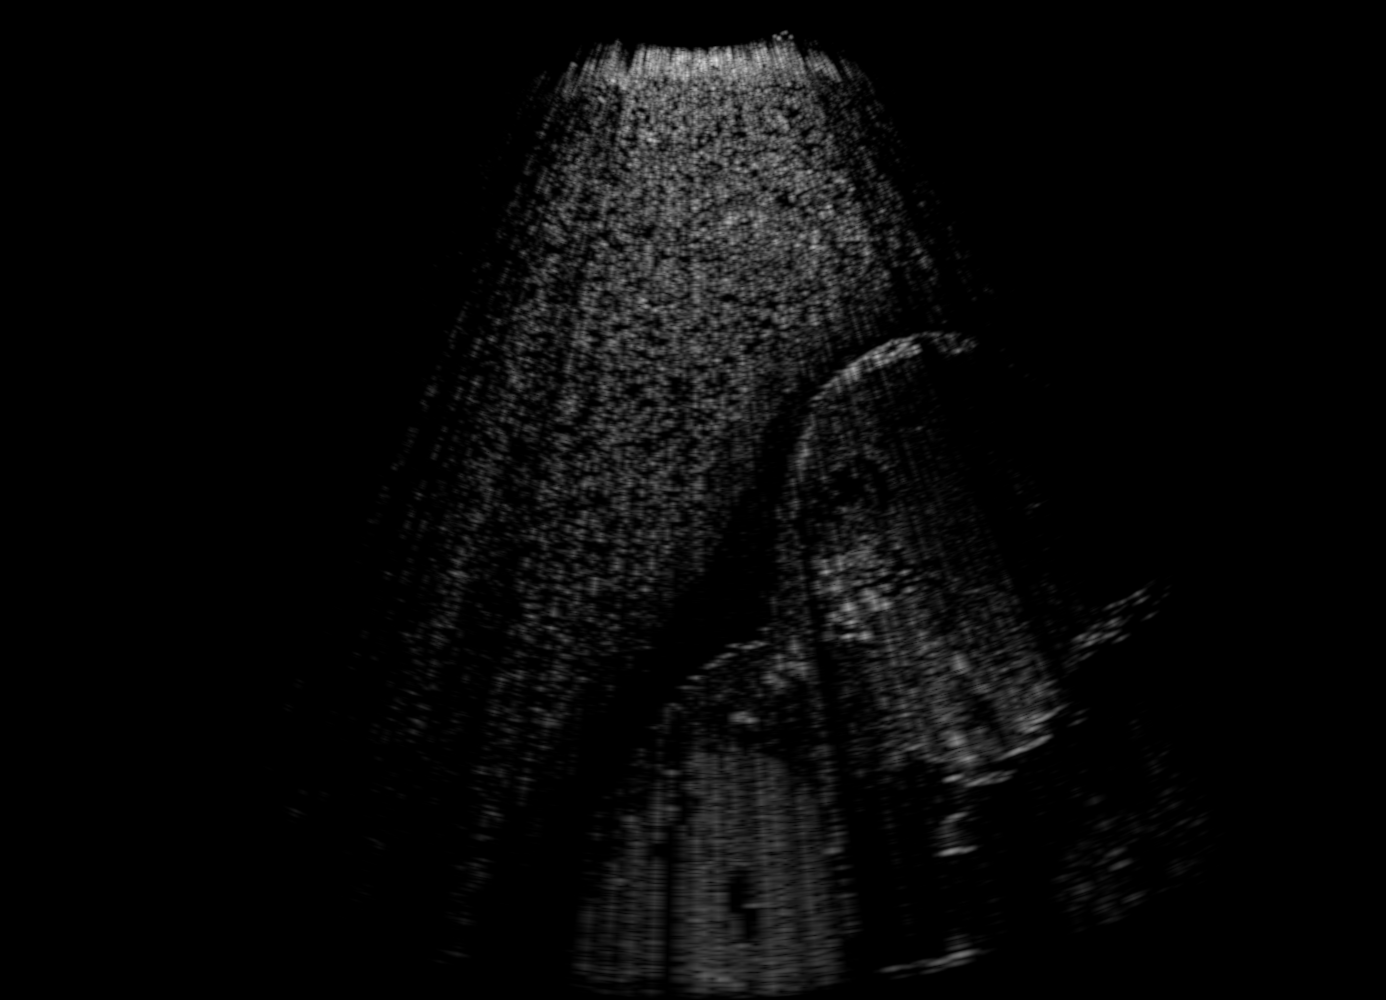

US images. For each regularly-sampled key frame of a simulated US fetal exam, paired low and high quality images are generated using two simulation passes: low quality images using one primary ray per US scanline and one elevational layer; and high quality images using 32 primary rays per scanline and three elevational layers [10]. Other simulation parameters are kept identical for both simulation passes, cf Table 1. Example B-mode images are shown in Fig. 1(a-b).

Segmentation Maps As additional input for our method, segmentation maps as the cross-section of input triangulated anatomical surfaces are also output by the simulation, corresponding to each low-/high-quality image, cf Fig. 1(c).

To approximate such attenuation effect, we create attenuation integral maps , accumulated for each image point along the respective ultrasound propagation path. For better dynamic range and to avoid outliers, these maps are normalized by the 98 %ile of image intensities and then scan-converted into the same Cartesian coordinate frame as the simulated B-mode images. Fig. 1(d) shows sample integral attenuation maps.

Qualitative Results. Fig. 3 shows a visual comparison of the three model variants on four examples. The baseline L2HM fails to preserve anatomical structures due to missing structural information in the input images. Resulting ambiguities in the network prediction cause artifacts such as blur in regions that feature fine details such as bones. Providing segmentation maps as additional input (L2HMS) greatly reduces such artifacts as shown in Fig. 3(c). However, L2HMS still struggles in modeling complex non-local features such as directional occlusion artifacts, note the lack of acoustic shadows in Fig. 3(c). In contrast, our final model L2HMSA is able to accurately synthesize these features and produces translations significantly closer to the target, as demonstrated in Fig. 3(d). In particular, our proposed model with segmentation and attenuation integral maps is able to recover both missing anatomical structures and directional artefacts.

Above image translation has been demonstrated on patches. For the entire field-of-view (FoV) US images, patch fusion from image translation of non-overlapping patches would cause artifacts at image seams. Averaging overlapping patches, on the other hand, would blur the essential US texture. Although seamless tiling of US images is possible using graphical models [3], this requires prohibitively long computation time. Herein, we instead directly apply our trained generator on full FoV low-quality images, since the generator is fully convolutional and thus can operate on images of arbitrary size. Fig. 4 shows two examples of translated images by L2HMS and L2HMSA, demonstrating direct inference on full FoV images. While anatomical structures are well preserved and the effect of attenuation integral map is apparent, speckle texture appearance is seen to degrade slightly especially in the top image regions, where the ultrasound texture looking particularly different due to focusing difference and near-field effects.

(a) Input

(b) L2HM

(c) L2HMS

(d) L2HMSA

(e) Target